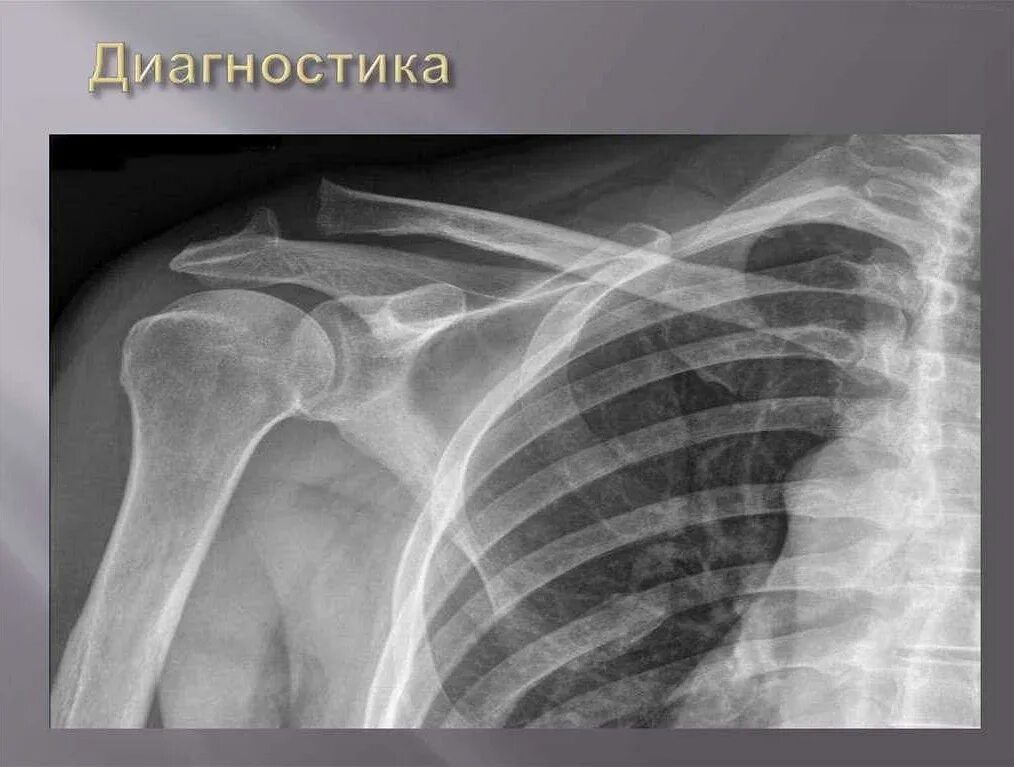

Деформирующий акромиально ключичного сочленения